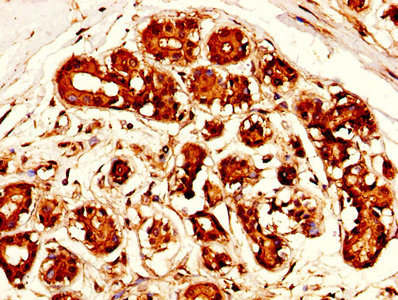

IHC image of CSB-PA10159A0Rb diluted at 1:300 and staining in paraffin-embedded human ovarian cancer performed on a Leica BondTM system. After dewaxing and hydration, antigen retrieval was mediated by high pressure in a citrate buffer (pH 6.0). Section was blocked with 10% normal goat serum 30min at RT. Then primary antibody (1% BSA) was incubated at 4°C overnight. The primary is detected by a biotinylated secondary antibody and visualized using an HRP conjugated SP system.

IHC image of CSB-PA10159A0Rb diluted at 1:300 and staining in paraffin-embedded human breast cancer performed on a Leica BondTM system. After dewaxing and hydration, antigen retrieval was mediated by high pressure in a citrate buffer (pH 6.0). Section was blocked with 10% normal goat serum 30min at RT. Then primary antibody (1% BSA) was incubated at 4°C overnight. The primary is detected by a biotinylated secondary antibody and visualized using an HRP conjugated SP system.